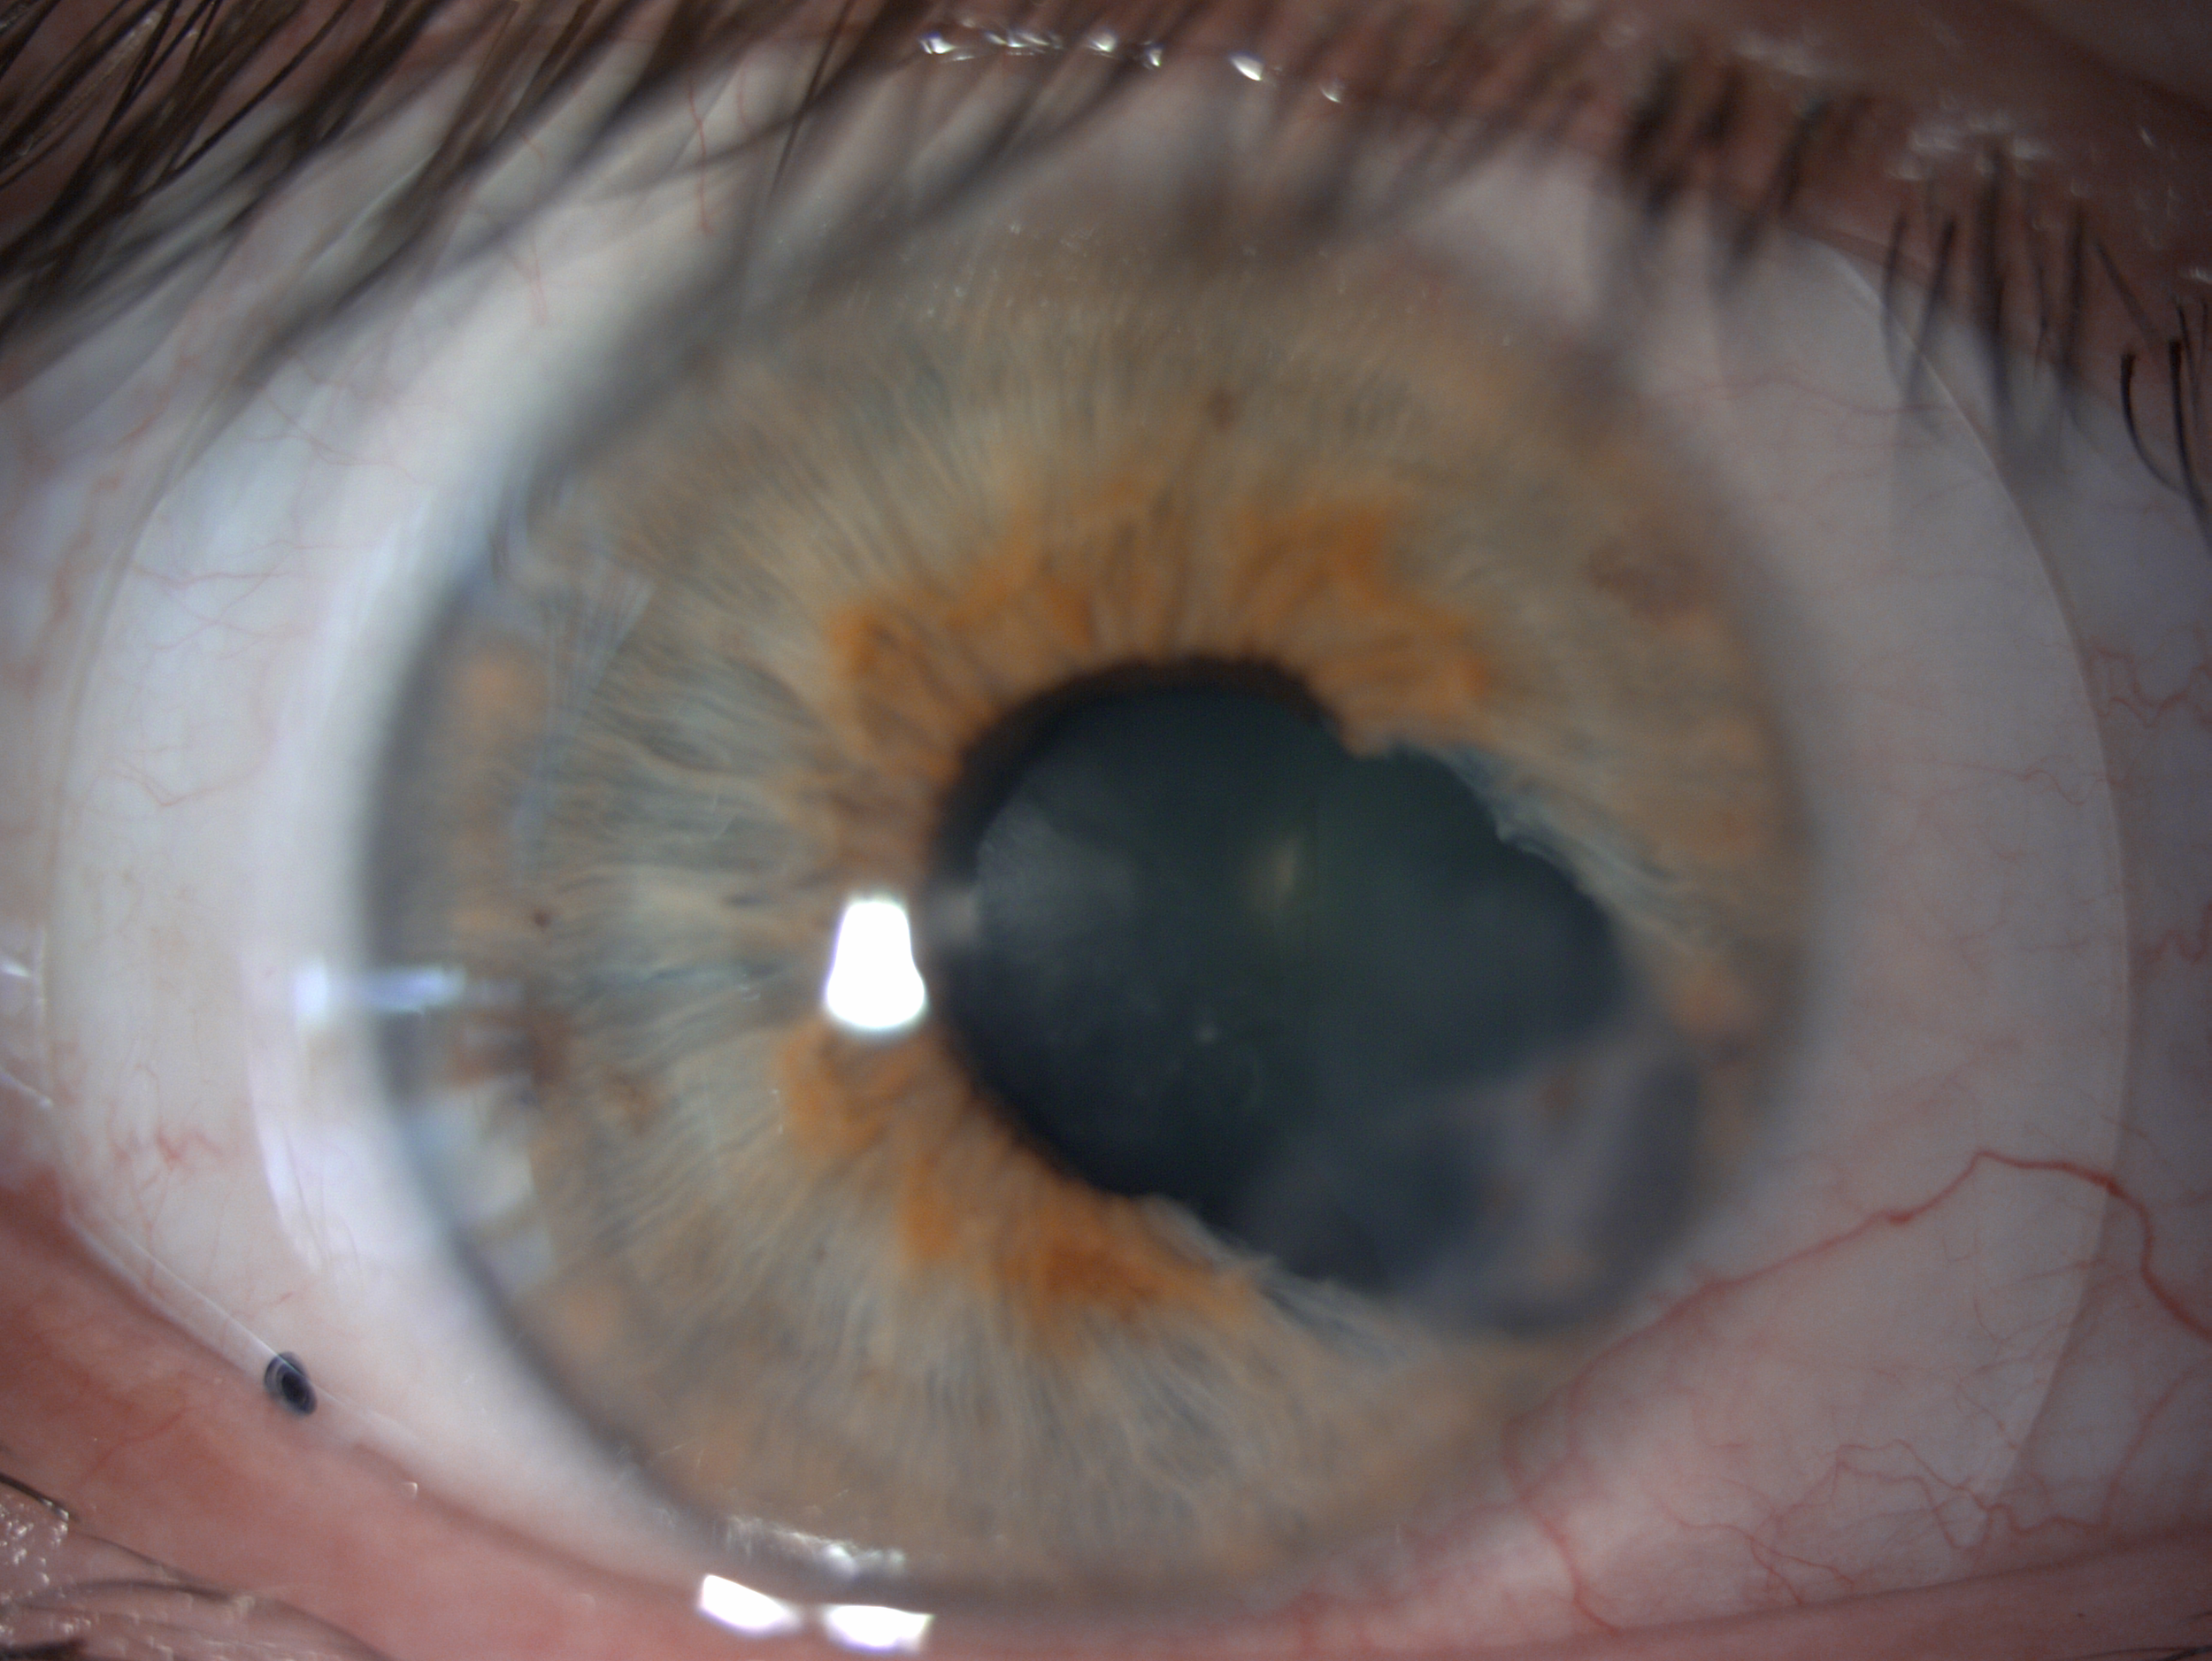

By vaulting over the eye with fluid, we are able to manage complicated eye conditions such as astigmatism, keratoconus, corneal transplants, severe dry eye, corneal scarring, LASIK complications and more. These lenses can be life changing.

A scleral lens consultation is the best place to start! Slam dunk cases tend to be those who have high astigmatism, irregular corneas, keratoconus, corneal scarring, corneal transplant, post-lasik, post-RK, severe dry eye, Sjogren’s Syndrome, and Bell’s Palsy.

At a scleral lens consultation, we will first learn and discuss your eye health history, take profilometry and topography scans, and discuss your needs. If you are new to scleral lenses, we will place a “demo” scleral lens on your eye(s) to check the vision potential of your eyes, as well as to see if your eyes feel better if your condition is related to dry eyes. If we determine that you are a candidate and proceed with scleral lenses, our doctor Dr. Seif then orders a unique, custom designed lens and adjusts it until the most optimal vision and fit is achieved.

For established wearers, we would assess your current prescription and utilize anterior segment OCT to assess the fit of your current lenses. We may also run aberrometry measurements to see if you would benefit from higher-order aberration correction. We would determine if your current lens design is appropriate healthwise, or if you would benefit from a different lens design.